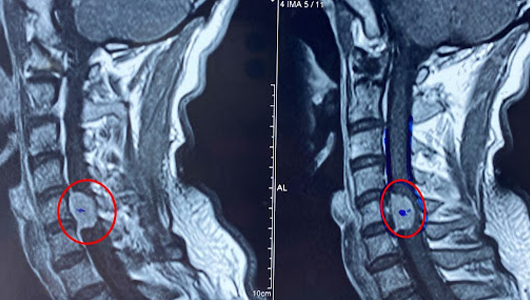

4.5. Cộng hưởng từ hạt nhân: